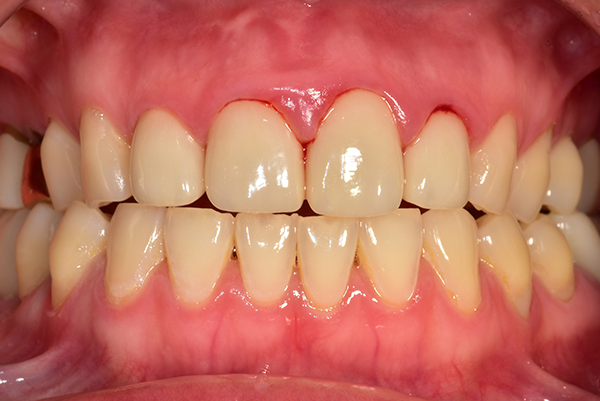

잇몸이 붉지 않고, 연분홍빛을 띠며 단단하게 치아를 감싸고 있습니다. 엑스레이 에서는 치아 뿌리를 따라 잇몸뼈가 치아 경계선 바로 아래까지 촘촘하게 유지되 고 있습니다.

잇몸이 붉지 않고, 연분홍빛을 띠며 단단하게 치아를 감싸고 있습니다. 엑스레이에서는 치아 뿌리를 따라 잇몸뼈가 치아 경계선 바로 아래까지 촘촘하게 유지되고 있습니다.